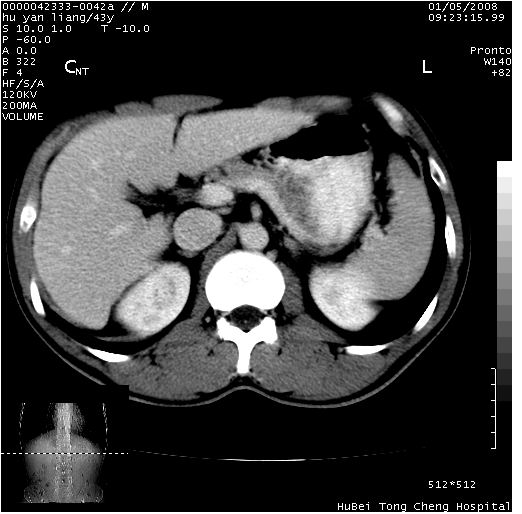

患者 男,43岁。右上腹不适1年余。既往有“肝右叶肝脓肿”病史,经保守治疗后痊愈。

b超提示:1)肝右叶肝内胆管结石。2)肝右叶占位性病变待排。

上中腹部ct轴位平扫+增强扫描(层厚10mm,螺距1.0,重建间隔10mm),图像如下:

肝右上叶偏后方较大团片状钙化灶,支持:肝脓肿后遗改变!

肝右叶后段团块状钙化灶,结合病史考虑肝脓肿痊愈后表现。